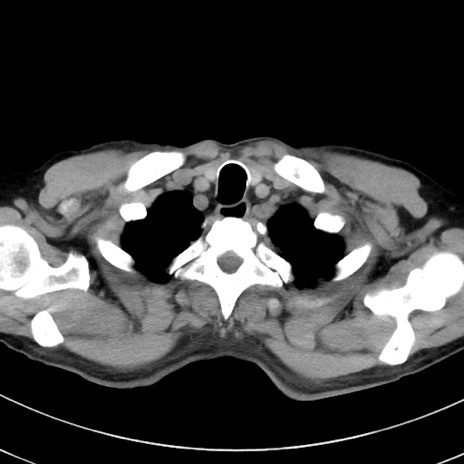

冠状断像